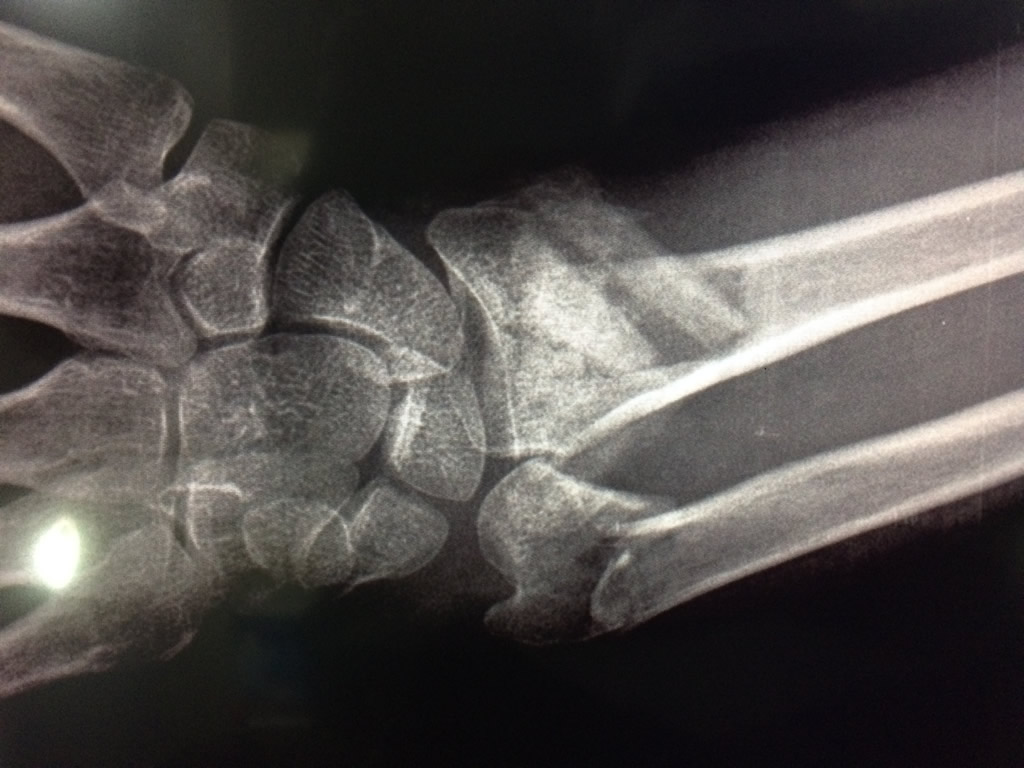

Cirugias en El Salvador - Cirugías de Muñecas y Manos

Los procedimientos más comunes en cirugía de la mano son aquellos destinados a reparar traumatismos, incluyendo lesiones de tendones, nervios, vasos sanguíneos, y articulaciones; huesos fracturados; y quemaduras, cortes, y otros daños de la piel.